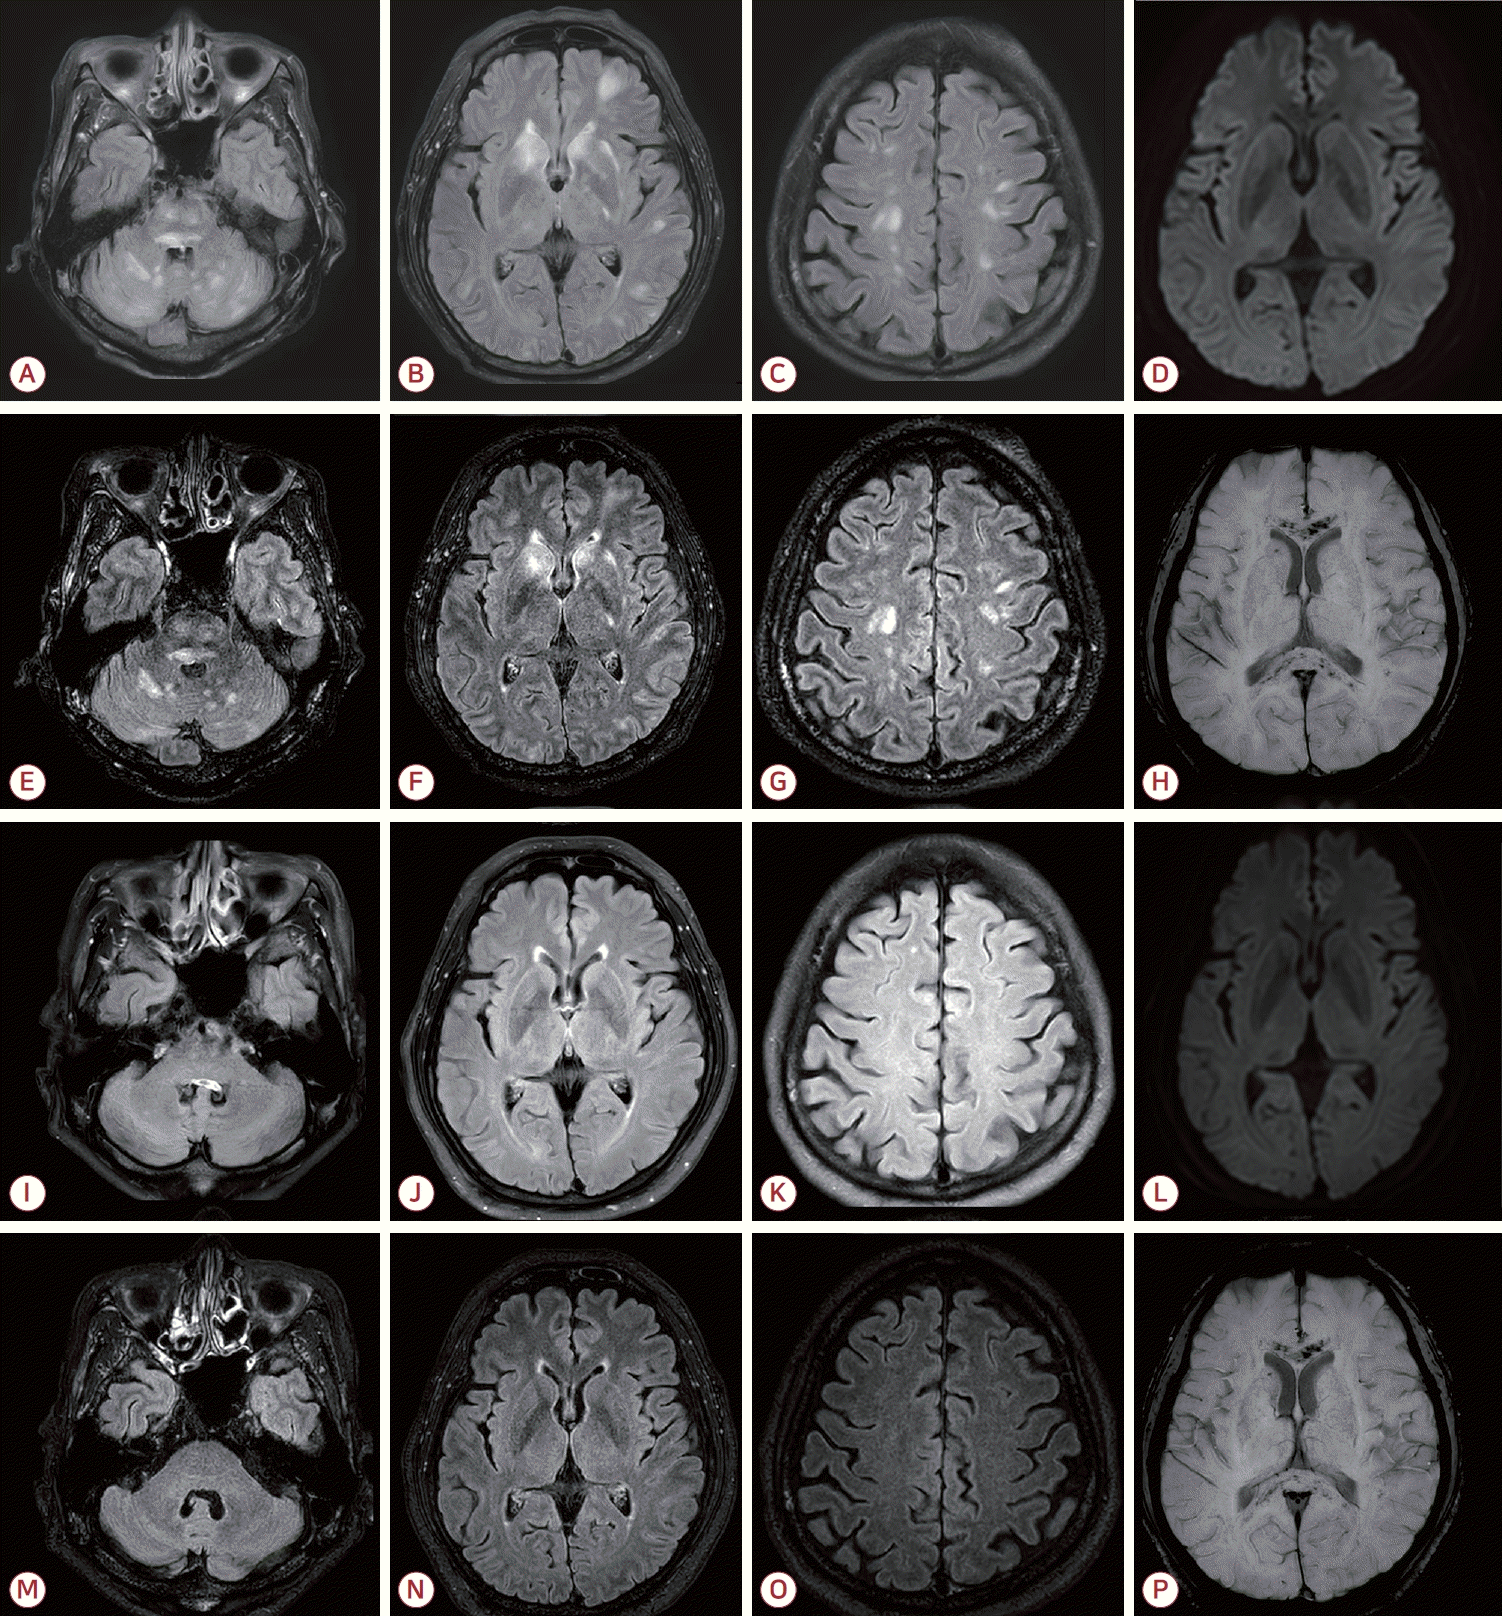

77세 남성이 하루 전부터 시작된 전신 쇠약감과 당일 발생한 의식 혼동을 주소로 응급실에 내원하였다. 환자는 5년 전 간세포암으로 우간 절제술을 받았으며 이후 우측 부신 전이가 확인되어 약 1년 전부터 3주 간격으로 총 17회에 걸쳐 아테졸리주맙과 베바시주맙 병합 요법을 받았고 마지막 투약은 내원 1개월 전이었다. 치료 기간 동안 특이 부작용은 없었으나 이후 추적 영상에서 하대정맥 침범을 동반한 재발과 다발 전이가 관찰되었다. 내원 당시 동공반사는 정상이었고 안구편위는 보이지 않았으며 근력은 정상이었다. 수막자극징후도 보이지 않았다. 혈압은 수축기 혈압이 170 mmHg 내외로 유지되었다. 말초혈액 검사에서 백혈구 3,700/mm3, 혈색소 10.4 g/dL, 혈소판 97,000/mm3로 경도의 범혈구감소증이 있었으며 혈중 암모니아는 135 μg/dL로 상승되어 있었다. 그 외 젖산, 소듐, C-반응단백 등은 정상 범위였고 뇌 computed tomography (CT)에서는 특이 소견이 없었다. 간성 혼수를 의심하여 관장 치료를 시행하였으나 의식 호전이 없어 뇌MRI를 시행하였다. MRI에서 뇌간, 소뇌, 심부회백질, 대뇌피질 및 피질하백질에 다발성 T2고신호강도 병변이 관찰되었고 조영증강액체감쇠역전회복(fluid attenuated inversion recovery, FLAIR)영상에서는 주로 뇌간과 소뇌, 일부 대뇌 반구에 작은 조영증강 결절이 확인되었다. 자화율강조영상(susceptibility weighted image, SWI)에서 뇌량과 양측 피질하백질에 광범위 미세출혈이 확인되었다(Fig. A-H). 뇌 전이 연관 탈수초질환이나 혈관염 가능성을 배제하기 위하여 뇌척수액 검사와 뇌파 검사를 시행하였으며 뇌척수액에서 세포 수 2/mm3, 단백질 92 mg/dL, 포도당 60 mg/dL로 경미한 단백 상승 소견이 있었고 세포 검사에서는 악성세포가 관찰되지 않았다. 항아쿠아포린-4항체, 자가면역항체 및 신생물딸림항체는 모두 음성이었다. 뇌파 검사에서는 전반적인 세타파 및 델타파가 관찰되었으나 뇌전증파는 없었다. 입원 4일째, 우측 반신마비와 발열(38℃)이 발생하여 경험적 항생제 치료를 시작하였다. 스테로이드 치료도 고려되었으나 다음날 의식 수준이 호전되었고 우측 마비도 완전히 회복되었다. 이후 재평가에서 경미한 구음장애가 있었으나 언어 기능은 거의 정상이었으며 입원 기간 동안의 사건전기억상실(retrograde amnesia)을 보였다. 추적 뇌파에서는 정상 배경파를 보였다. 환자는 재활 치료 후 신경계 후유증 없이 퇴원하였다. 퇴원 4개월 후 시행한 추적 MRI에서 대뇌, 뇌간, 소뇌의 다발성 고신호강도 병변은 거의 소실되었으나 광범위 미세출혈은 지속되었다(Fig. I-P).

Initial brain MRI demonstrated multiple T2/FLAIR hyperintense lesions involving the brainstem, cerebellum, deep gray matter, cerebral cortex, and subcortical white matter (A-C). Diffusion-weighted imaging (D) showed no diffusion restriction. Contrast-enhanced FLAIR images revealed multiple tiny enhancing nodules, predominantly in the brainstem and cerebellum, and to a lesser extent in the cerebral hemispheres (E-G). SWI showed diffuse microbleeds in the corpus callosum and subcortical white matter (H). On follow-up MRI after 4 months, most hyperintense lesions had resolved (I-K, M-O). Diffusion-weighted imaging again showed no diffusion restriction (L). Contrast- enhanced FLAIR demonstrated interval disappearance of the previously noted tiny enhancing nodules (M-O). However, diffuse microbleeds persisted in the corpus callosum and subcortical regions (P). MRI; magnetic resonance imaging, FLAIR; fluid-attenuated inversion recovery, SWI; susceptibility-weighted imaging.